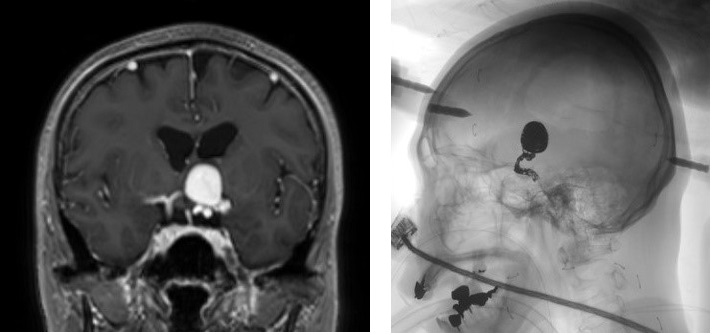

左:頭部MRI、右:治療後、血管内コイル塞栓術術後